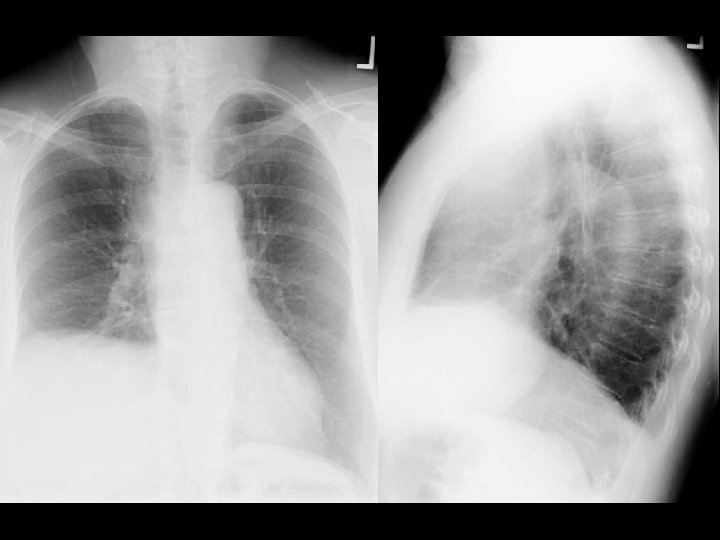

Left hydropneumothorax • Findings: – left pnuemothorax – left pleural effusion (possibly blood) • causes: – penetrating trauma – iatrogenic – bronchopleural fistula